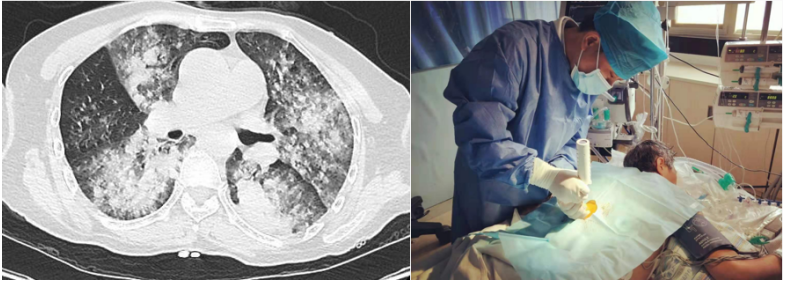

患者,女,50岁;活动后喘息20天,加重伴发热3天,2021年11月19日转入我院。入院胸部CT显示:双肺实变,磨玻璃影(图1)。11月24日复查胸部CT可见病变进展迅速(图2)。予患者气管插管机械通气、俯卧位等,呼吸衰竭未见改善。遂于11月25日启动VV-ECMO(转速2860 rpm,流量4.5 L/min,氧浓度100%)。追问病史:患者入院前1月有活动后气促症状,自觉全身不适,近2年有眼干、口干不适。进一步检查发现,ANA反应阳性(+),ANA核型为胞浆颗粒型(异常);抗SSA/Ro抗体阳性(++)、抗Ro-52抗体阳性(+++)。诊断:急性间质性肺炎(AIP);Ⅰ型呼吸衰竭;混合性结缔组织病。治疗:VV-ECMO+呼吸机辅助通气+俯卧位通气、激素(甲强龙80 mg×7天,60 mg×3天,40 mg qd)、免疫抑制剂(环磷酰胺400 mg qd×3天)、抗感染(哌拉西林他唑巴坦4.5 g q12h+莫西沙星0.4 g qd+氟康唑氯化钠注射液20 mg qd)、抗凝等。在随后的一段时间内,患者影像学改善不明显(图3)。直至12月20日,复查胸部CT可见患者肺部病变较前明显吸收(图4)。2021年12月31日VV-ECMO撤机后,继续气切呼吸机辅助通气,甲强龙40 mg qd抗炎治疗,继续抗感染治疗,2022年1月7日脱机,1月21日气管封管,1月26日出院。后续治疗:强的松25 mg qd,环磷酰胺600 mg q2w×4次,序贯吗替麦考酚酯0.5 g bid。重症间质性肺疾病(ILD)在诊断方面需要考虑以下问题:是ILD吗?是哪种ILD?严重程度如何?在治疗方面,除了生命支持(呼吸支持重点)和病因治疗,并发症的处理也至关重要。重症ILD的诊断包括两方面,一方面是通过影像学、病史+临床表现、BALF-NGS、实验室检查、肺活检等对ILD进行诊断;另一方面涉及重症,患者多面临呼吸衰竭甚至多器官衰竭,因此时间更加紧迫。在ICU内最常见的重症ILD包括:特发性肺纤维化急性加重(AE-IPF)、自身免疫相关性ILD、肿瘤治疗相关性ILD、隐源性机化性肺炎(COP)、AIP、过敏性肺炎(HP)、急性嗜酸性粒细胞性肺炎(AEP)、药物相关ILD等。在影像学方面,最易导致重症的类型有弥漫性磨玻璃影和实变影。最常见的鉴别诊断就是重症肺部感染。表现为弥漫性磨玻璃影或实变影的ILD较为多见,例如:HP、嗜酸性粒细胞性肺炎(EP)、结缔组织病相关间质性肺病(CTD-ILD)、非特异性间质性肺炎(NSIP)、脱屑性间质性肺炎(DIP)、淋巴细胞性间质性肺炎(LIP)、机化性肺炎(OP)、AE-IPF、肺泡蛋白沉积症(PAP)、肺泡微结石症、结节病、弥漫性肺泡出血综合征、肺水肿等。而很多感染性疾病影像学也可表现为磨玻璃影,例如:卡氏肺孢子菌肺炎(PCP)、病毒性肺炎、巨细胞病毒性肺炎、支原体肺炎。尽管如此,ILD也有部分影像学具有特征性,可以被识别。图5左表现为肺陷闭,也称为“猪头肉冻征”,这是典型的亚急性HP的影像学特征。图5右表现为弥漫性磨玻璃影,但以肺门向外扩展,外面有肺大泡,这是典型的PCP表现。临床上多见自身免疫性疾病导致的ILD,此类疾病也具有共同的特征,例如双肺弥漫,病理方面以NSIP或OP为主要特征。但也有部分患者可以出现弥漫性肺泡损伤(DAD)特征。如图6所示,左图为ANCA相关性血管炎,右图为MDA5相关性间质性肺病。因此,一定要警惕容易发生这种病理改变的自身免疫性疾病。